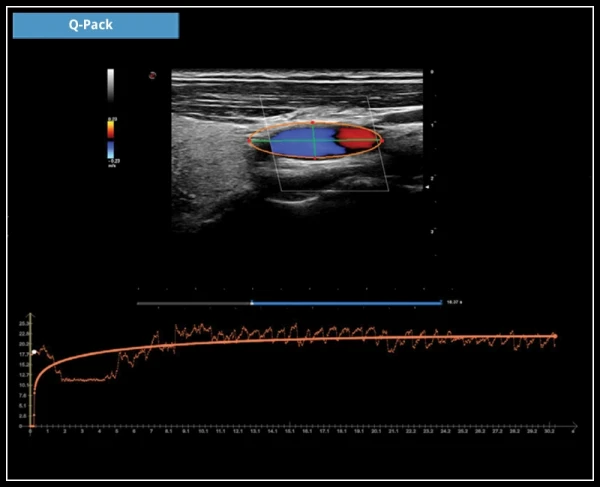

Q-Pack: Q-Pack – это новый мультимодальный инструмент для количественного анализа кривых Контрастной Перфузии (Wi/Wo), с применением Цветного, Энергетического Допплера и технологии CnTI™.